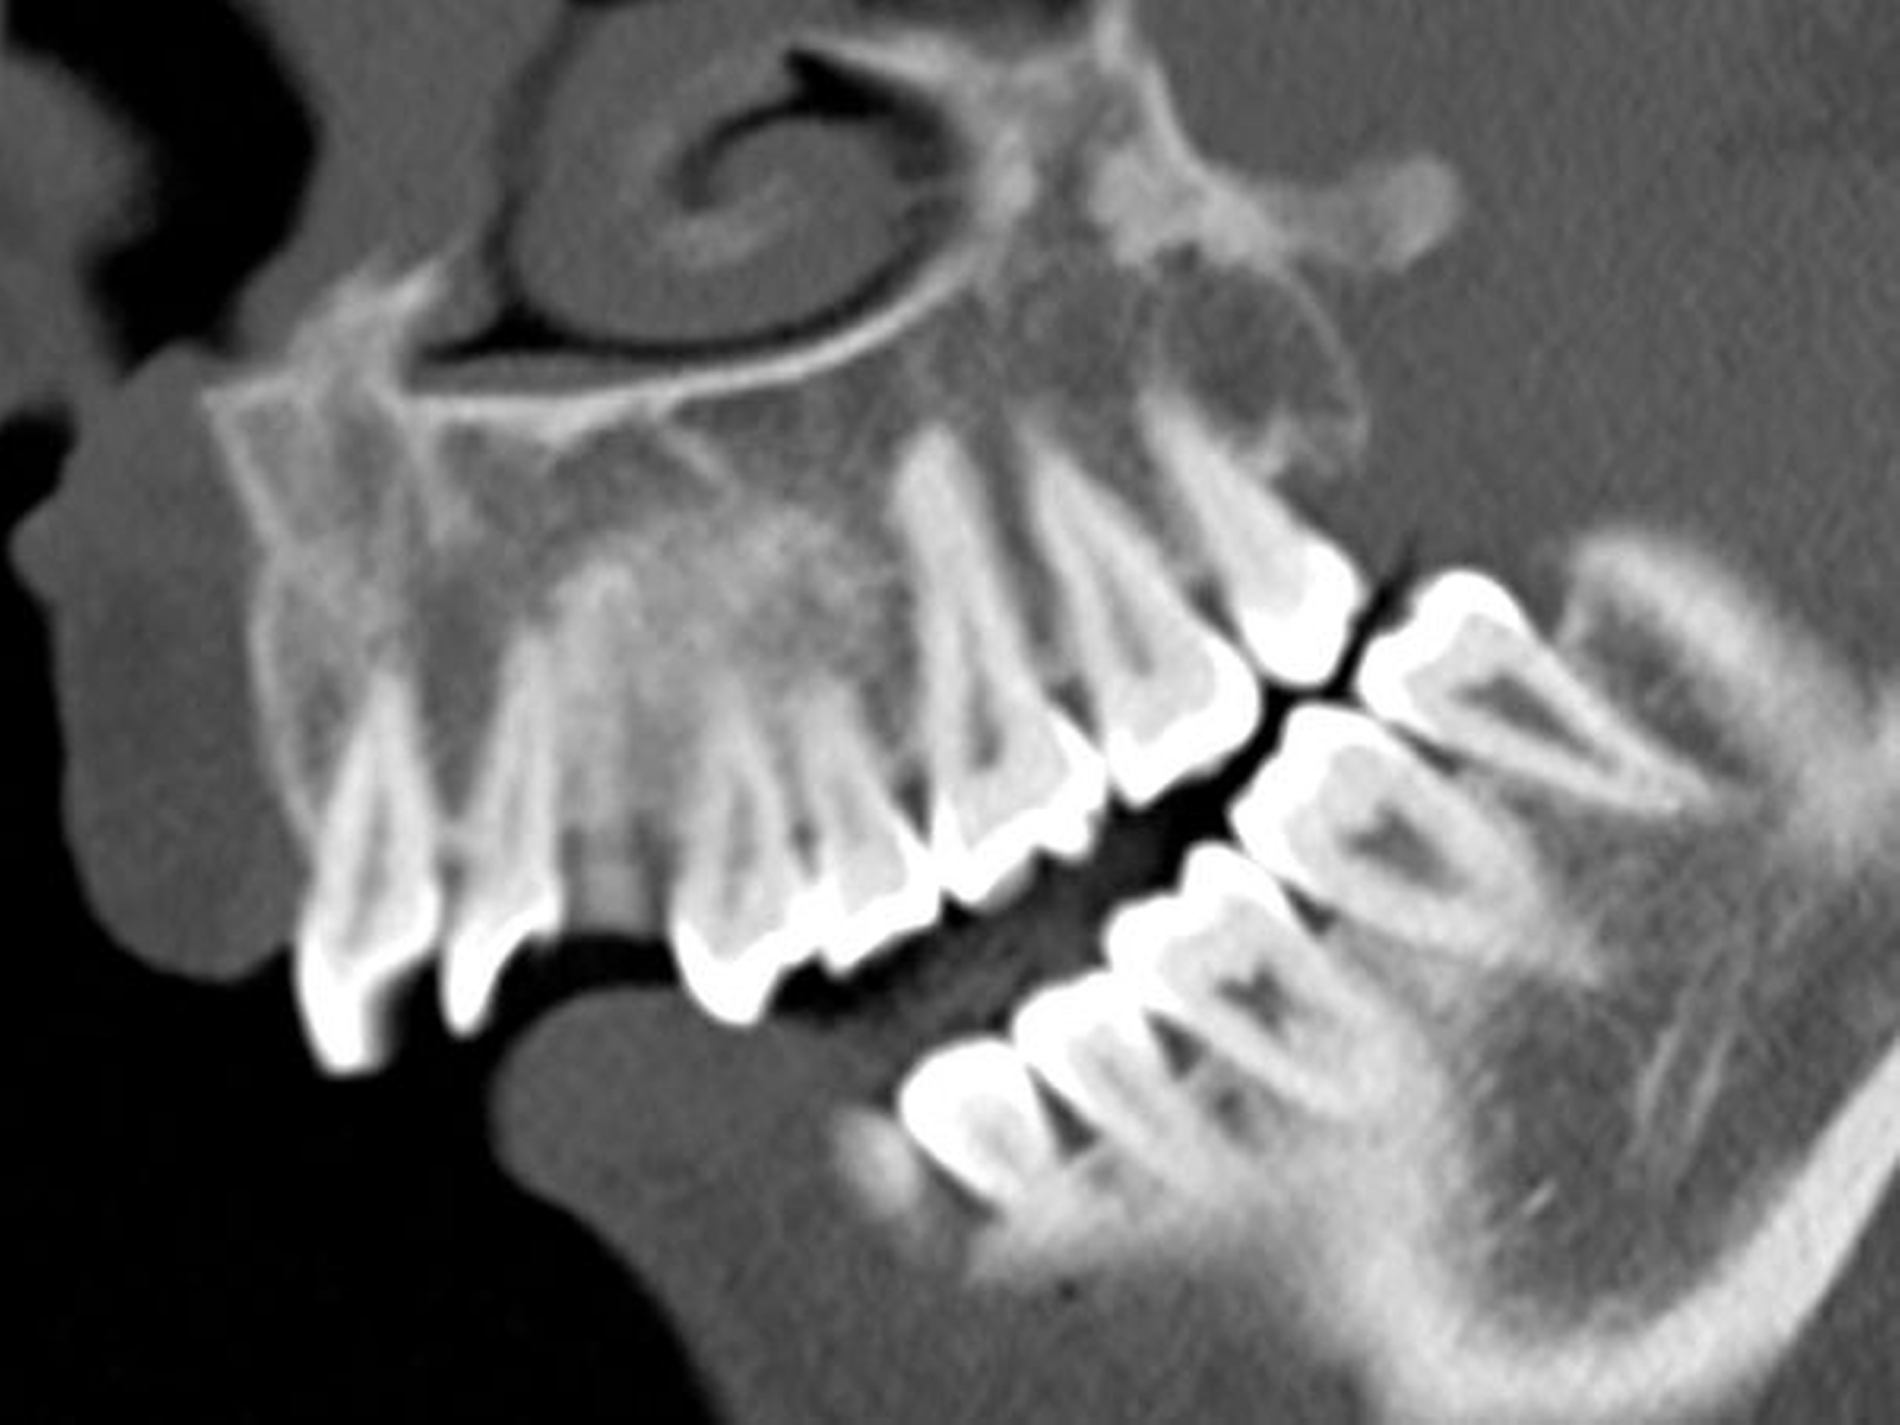

Eine 22-jährige Patientin stellte sich in unserer Schmerzambulanz zur weiteren Therapie vor. Sie beklagte eine reduzierte Mundöffnung, eine Druckdolenz im Bereich der Kaumuskulatur und ein „knisterndes“ Geräusch im Bereich des linken Kiefergelenkes. Bei der intraoralen Inspektion, die sich aufgrund der Mundöffnung als herausfordernd erwies (Abbildung 1), konnten weder hart- noch weichgewebliche Pathologien festgestellt werden.

Ein klinischer Hinweis auf eine mögliche Dentitio difficilis in regio 038, die die Patientin vermutet hatte, konnte nicht gefunden werden. Zur weiteren Diagnostik wurde ein Kopf-CT angefertigt, das eindrücklich die massiv eingeschränkte interokklusale Distanz im Molarenbereich demonstriert (Abbildung 2).